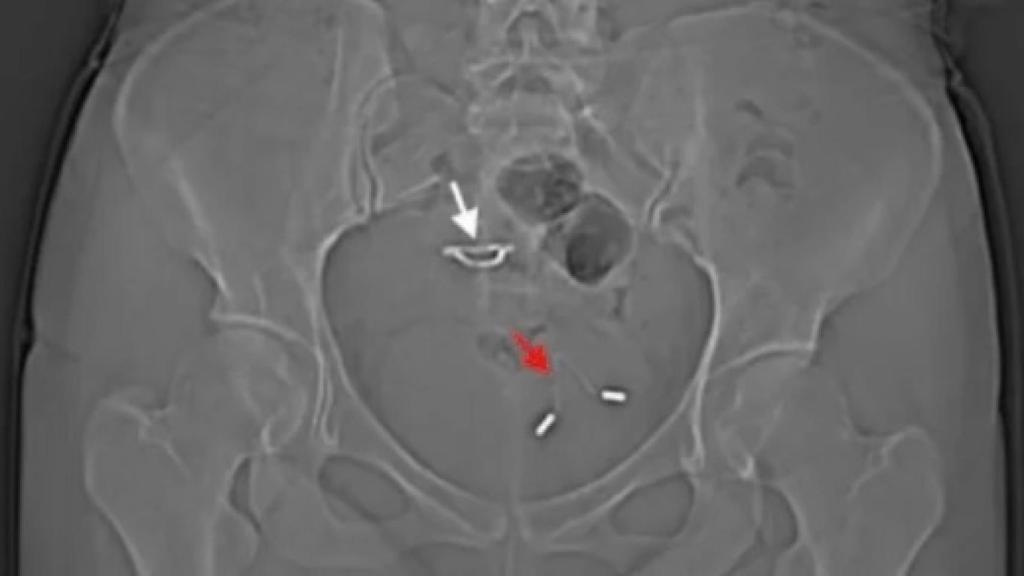

Una radiografía muestra el DIU en el interior de la vejiga de la paciente.

La verdadera explicación al suceso llegó cinco años después, cuando la paciente acudió a los servicios de urgencias aquejada de dolor abdominal, frecuencia excesiva en la micción y restos de sangre en la orina. Al hacer una radiografía de su pelvis, los sanitarios descubrieron que aquel DIU perdido había salido del útero y había acabado en la vejiga, dónde había comenzado a causar problemas crónicos.